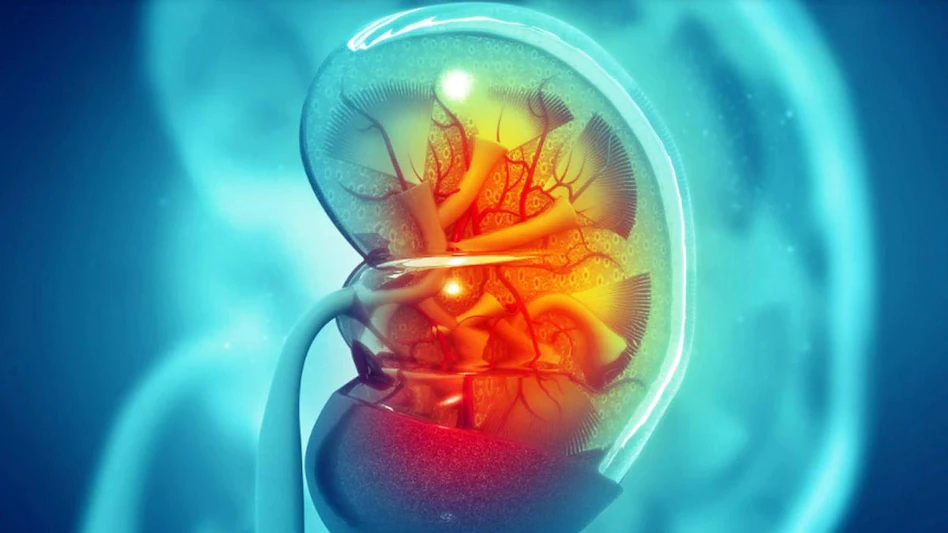

पेट र कम्मरको दुखाइ मिर्गौला पत्थरीको लक्षण

मिर्गौलामा पत्थरी हुँदा असहनीय पीडा हुन्छ । मिर्गौलामा पत्थरी हुँदा पेट र कम्मर दुख्छ । मिर्गौलामा विभिन्न कारणले पत्थरी बन्छ । विशेषज्ञका अनुसार पानी कम पिउनु नै पत्थरीको मुख्य कारण हो । यसका साथै, गलत खानपान पनि पत्थरी बन्ने कारण हुनसक्छ । चिकित्सकहरुले खानपानमा सुधार गर्दा पत्थरीको समस्या कम हुने बताउँछन् ।

मिर्गौलाको पत्थरीबाट बच्नका लागि दैनिक जीवनयापनका क्रममा के के सुधार ल्याउन सकिन्छ ?